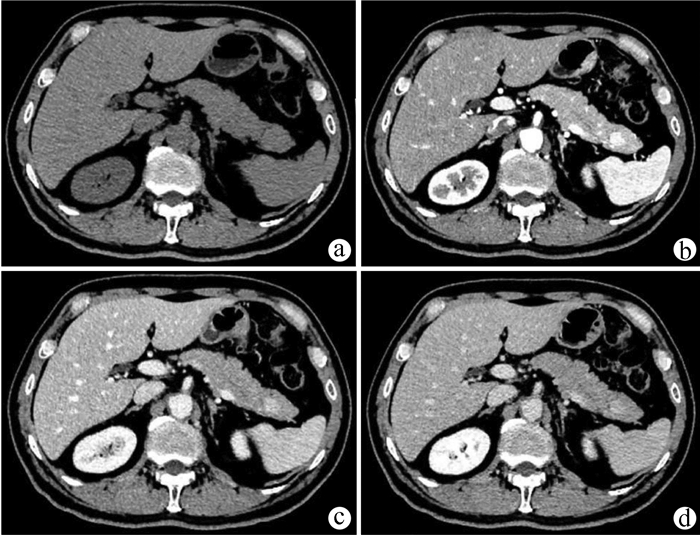

肝脏遗传性出血性毛细血管扩张症1例报告

王婷婷, 马亮, 陈建平

2022, 38(2): 423-425. DOI: 10.3969/j.issn.1001-5256.2022.02.032

摘要(1110) HTML (367) PDF (2696KB)(54)

摘要: